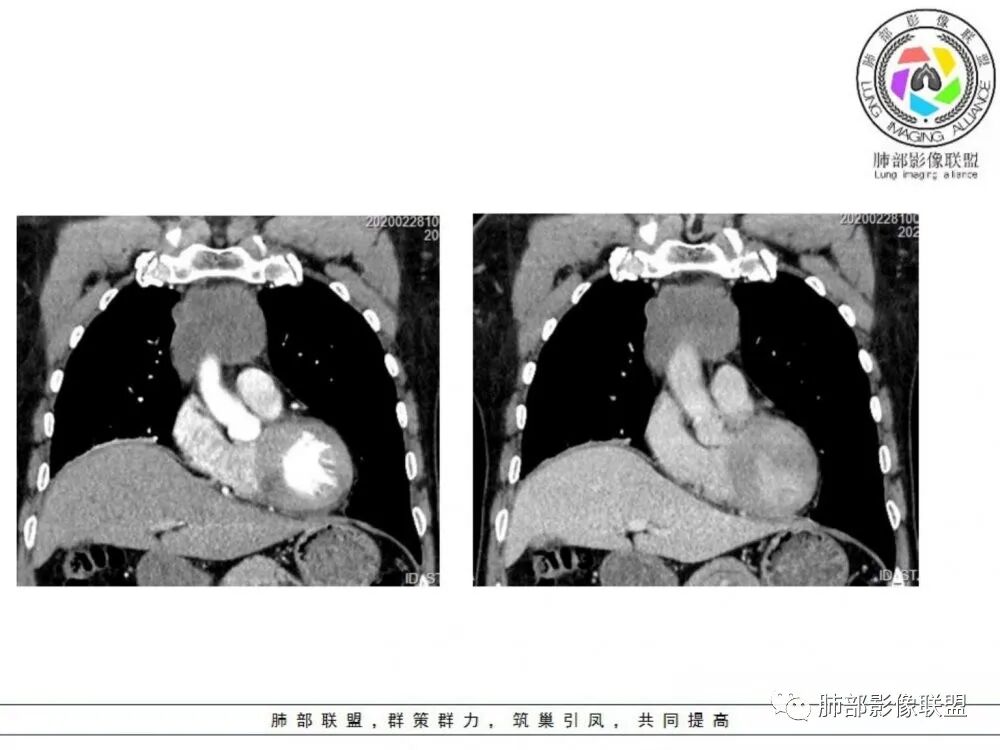

男性患者,65岁,前胸后背疼痛一个月。影像学前上纵隔分叶状的软组织肿块,肿块形态怪异,偏软,位于大血管间隙前,并有向血管后间隙发展的趋势,平扫CT值为40左右,增强扫描中心部未见强化,周围轻度的强化,约为50左右。前上纵隔的疾病谱包抬胸廓内甲状腺肿、胸腺瘤/癌、畸胎瘤、淋巴瘤。少见的心包囊肿或支气管囊肿。根据肿块的形态及强化特点,首先还是排除了胸内甲状腺肿及胸腺来源的肿物,这类的肿物强化比较明显。畸胎瘤成分比较复杂,具有软组织钙化或者脂肪类的组织,这个肿物虽然在平扫的时候好像有斑点状的钙化灶,但是总体成分还是比较单一,所以还是排除畸胎瘤的诊断。所以这样的情况是考虑:淋巴类的肿瘤,注意排除心包的囊肿或支气管来源的囊肿。

老年男性患者,前膈软组织肿块,边缘轮廓不光整,边界似乎尚清晰,内见小点状钙化灶,平扫密度欠均匀,增强后轻度强化表现,边缘有些斑片状的高强化区。综合考虑胸腺瘤或胸腺鳞癌,神经内分泌癌强化弱了一些。患者年龄较大,生殖细胞肿瘤不考虑,淋巴瘤血管包绕不够,可能性不大

前纵隔胸腺区分叶状软组织肿块影,轻度不均匀强化,中心可见坏死,边缘不清,病灶与邻近心包见条索影,上腔静脉受侵,上纵隔多发小淋巴结,考虑胸腺鳞癌可能。

中老年男性,前纵隔占位,基本居中,向两侧生长;边缘膨隆分叶,部分边界不清,增强不均匀轻中度强化,坏死区边界不清;周围多发增大淋巴结,考虑恶性。主要在胸腺癌、胸腺瘤、淋巴瘤之间鉴别。病灶偏软,有钻缝样生长,这些征象偏向于淋巴瘤。但此例老年患者,病灶内有点状钙化,缺乏结节堆砌感,倾向胸腺癌诊断。

2、侵袭性胸腺瘤:肿块与纵隔诸器官脂肪间隙消失,血管变形移位,可见心包积液,胸膜受累类似胸膜间皮瘤。